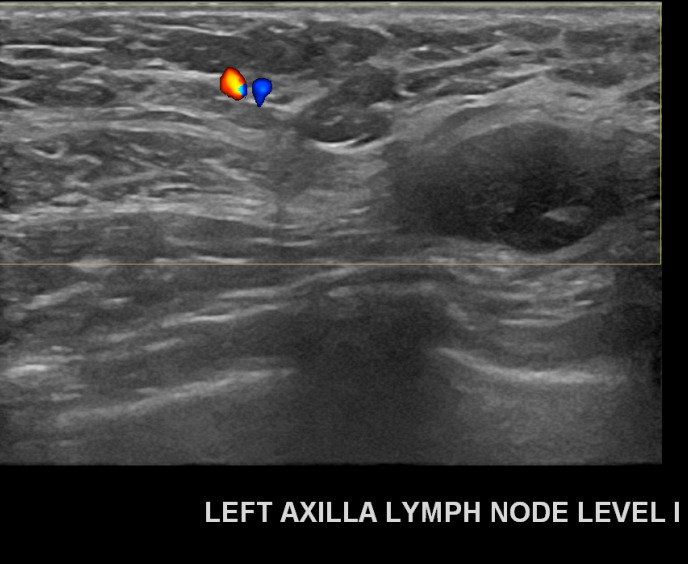

아산유외과개원후 679번째 유방암진단

상기환자 외부검사상 이상소견으로 내원하신 30대여성으로 좌측에 의심스러운혹과 전이된 림프절에 조직검사시행해 유방암 진단되었습니다.